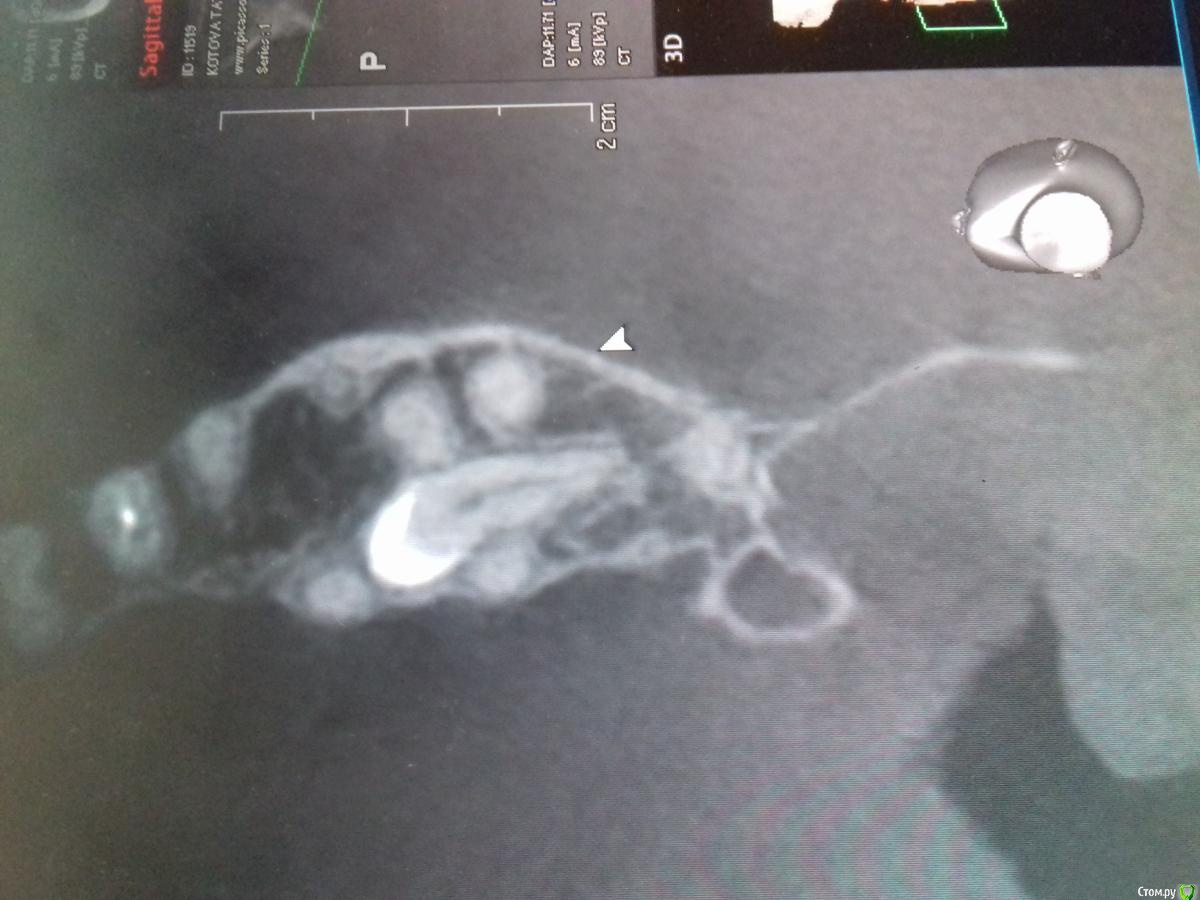

Jurai Опубликовано 29 декабря, 2016 Поделиться Опубликовано 29 декабря, 2016 А эта восьмерка спряталась лучше всех 1 Ссылка на комментарий

diesel87 Опубликовано 30 декабря, 2016 Поделиться Опубликовано 30 декабря, 2016 А эта восьмерка спряталась лучше всехIMG-20161228-WA0002.jpegIMG-20161228-WA0006.jpegIMG-20161228-WA0004.jpegСерьезно легла, убирать будете? Ссылка на комментарий

Jurai Опубликовано 30 декабря, 2016 Поделиться Опубликовано 30 декабря, 2016 А зачем, это случайная находка. Пусть лежит. 1 Ссылка на комментарий